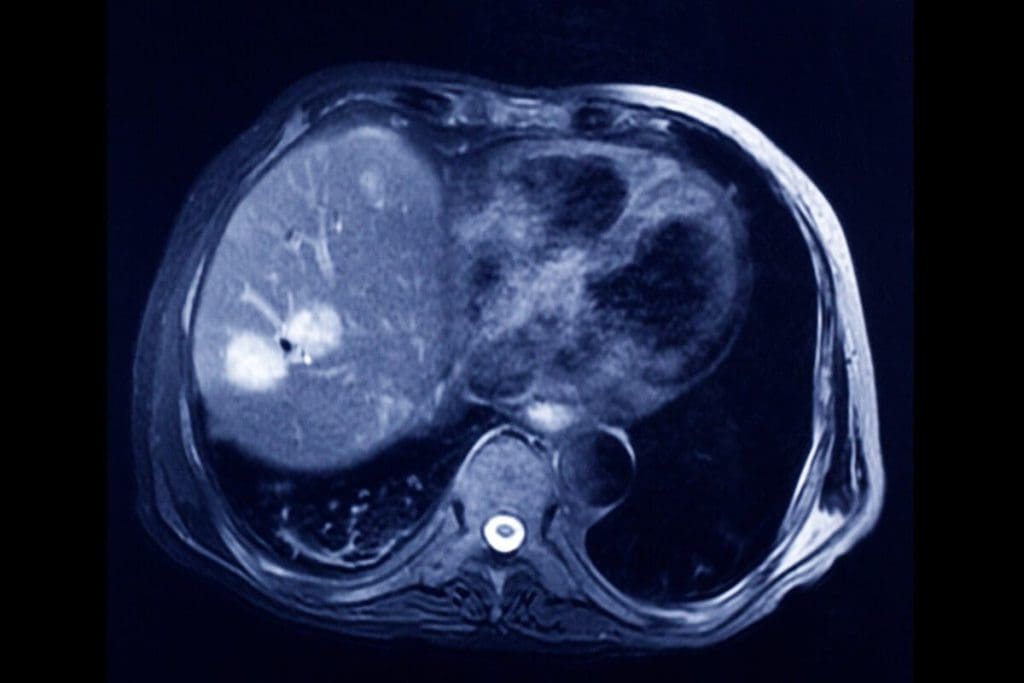

Alternative to CT Urogram: Does a CT Scan Detect Tumors?

A CT urogram is a common test for the urinary system that uses a CT scan and dye to visualize the kidneys, bladder, and ureters. However, for people at low risk, safer and cheaper alternatives like renal and bladder ultrasound, contrast-enhanced ultrasound, and voiding urosonography are effective options to diagnose urinary problems without requiring a CT scan. For those wondering, does a CT scan detect tumors? The answer is yes”CT scans are highly effective at identifying many types of tumors with good accuracy, although some small or low-grade tumors might be missed. While MRI generally offers higher sensitivity and specificity, CT remains a valuable and accessible tool for tumor detection.

A CT urogram uses a CT scanner to image the kidneys, ureters, and bladder. A contrast dye is given to make the urinary tract stand out. This helps find tumors, stones, and blockages.

One big drawback of a CT urogram is the radiation exposure. Though the radiation is controlled, it can slightly raise the risk of cancer later. Patients often ask, “does a CT scan detect tumors? Yes, it can ” but weighing the risks and benefits is important.

Doctors consider safer options when possible, especially if frequent imaging is expected. Still, the ability of CT to detect tumors is one reason it’s often chosen in high-risk cases. When evaluating bladder or kidney issues, many wonder, “does a CT scan detect tumors better than other scans?” In many scenarios, it does.